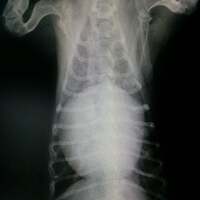

『心臓病』

ワンちゃんも高齢になってくるといろいろな病気がでてきます  元気そうに見えてもご飯はちゃんと食べていても  病魔がどんどん大きくなりつつあることがあります…